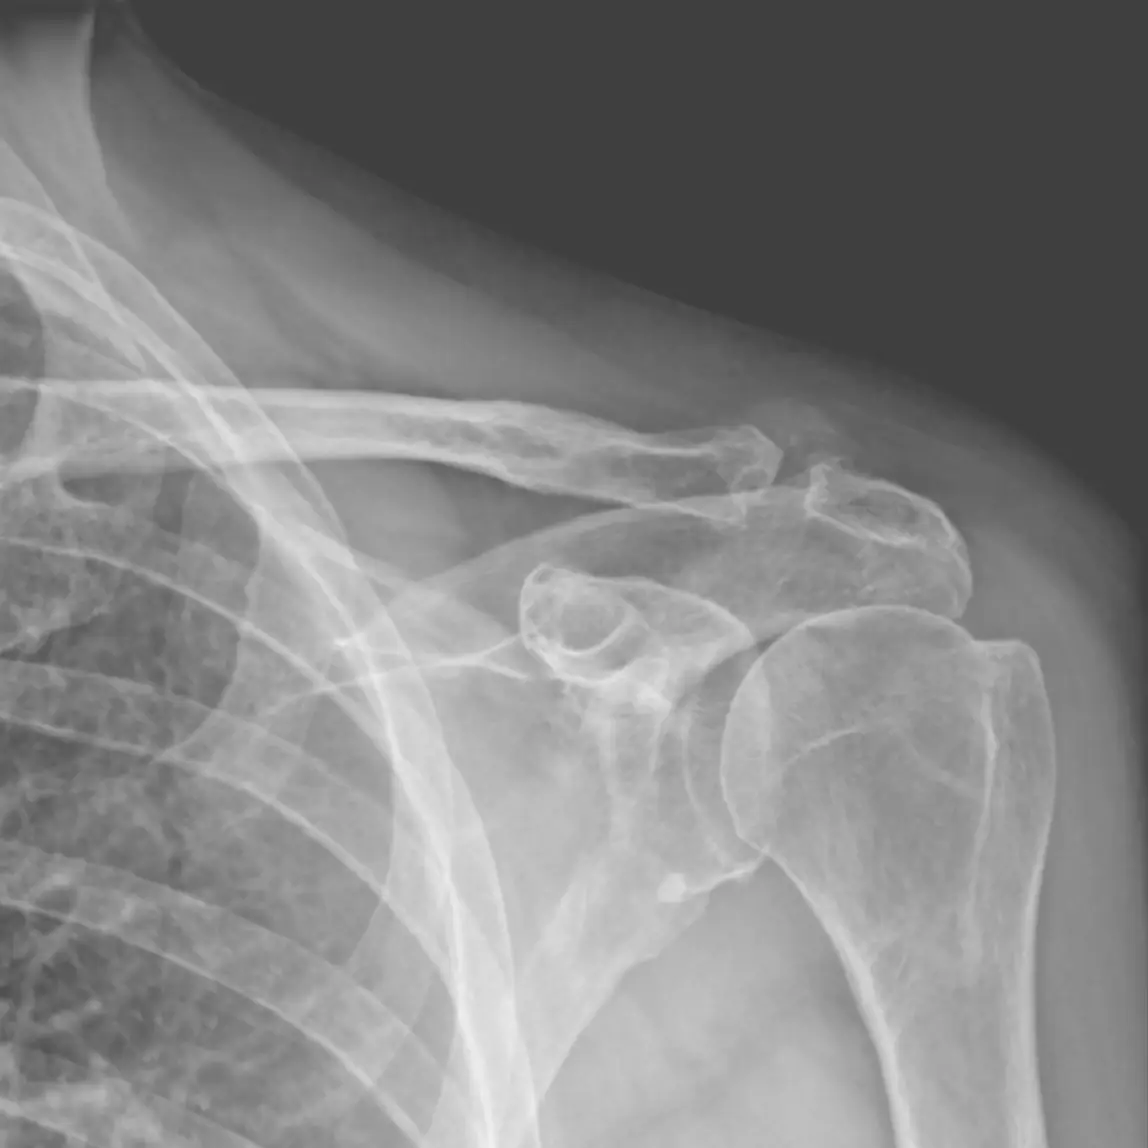

- Uszkodzenia stożka rotatorów

- Zapalenia kaletki podbarkowej

- Konfliktu podbarkowego (tzw. ciasnoty barkowej)

📌 Moja fizjoterapia barku to nie tylko „ćwiczenia”. Opieram ją na nowoczesnych metodach, takich jak terapia manualna, która przywraca prawidłową ruchomość w stawie, terapia tkanek miękkich, która rozluźnia napięte struktury czy terapia powięziowa (Fascial Manipulation). Indywidualnie dobrane ćwiczenia celują prosto w źródło problemu, wzmacniając osłabione mięśnie i zapobiegając nawrotom.